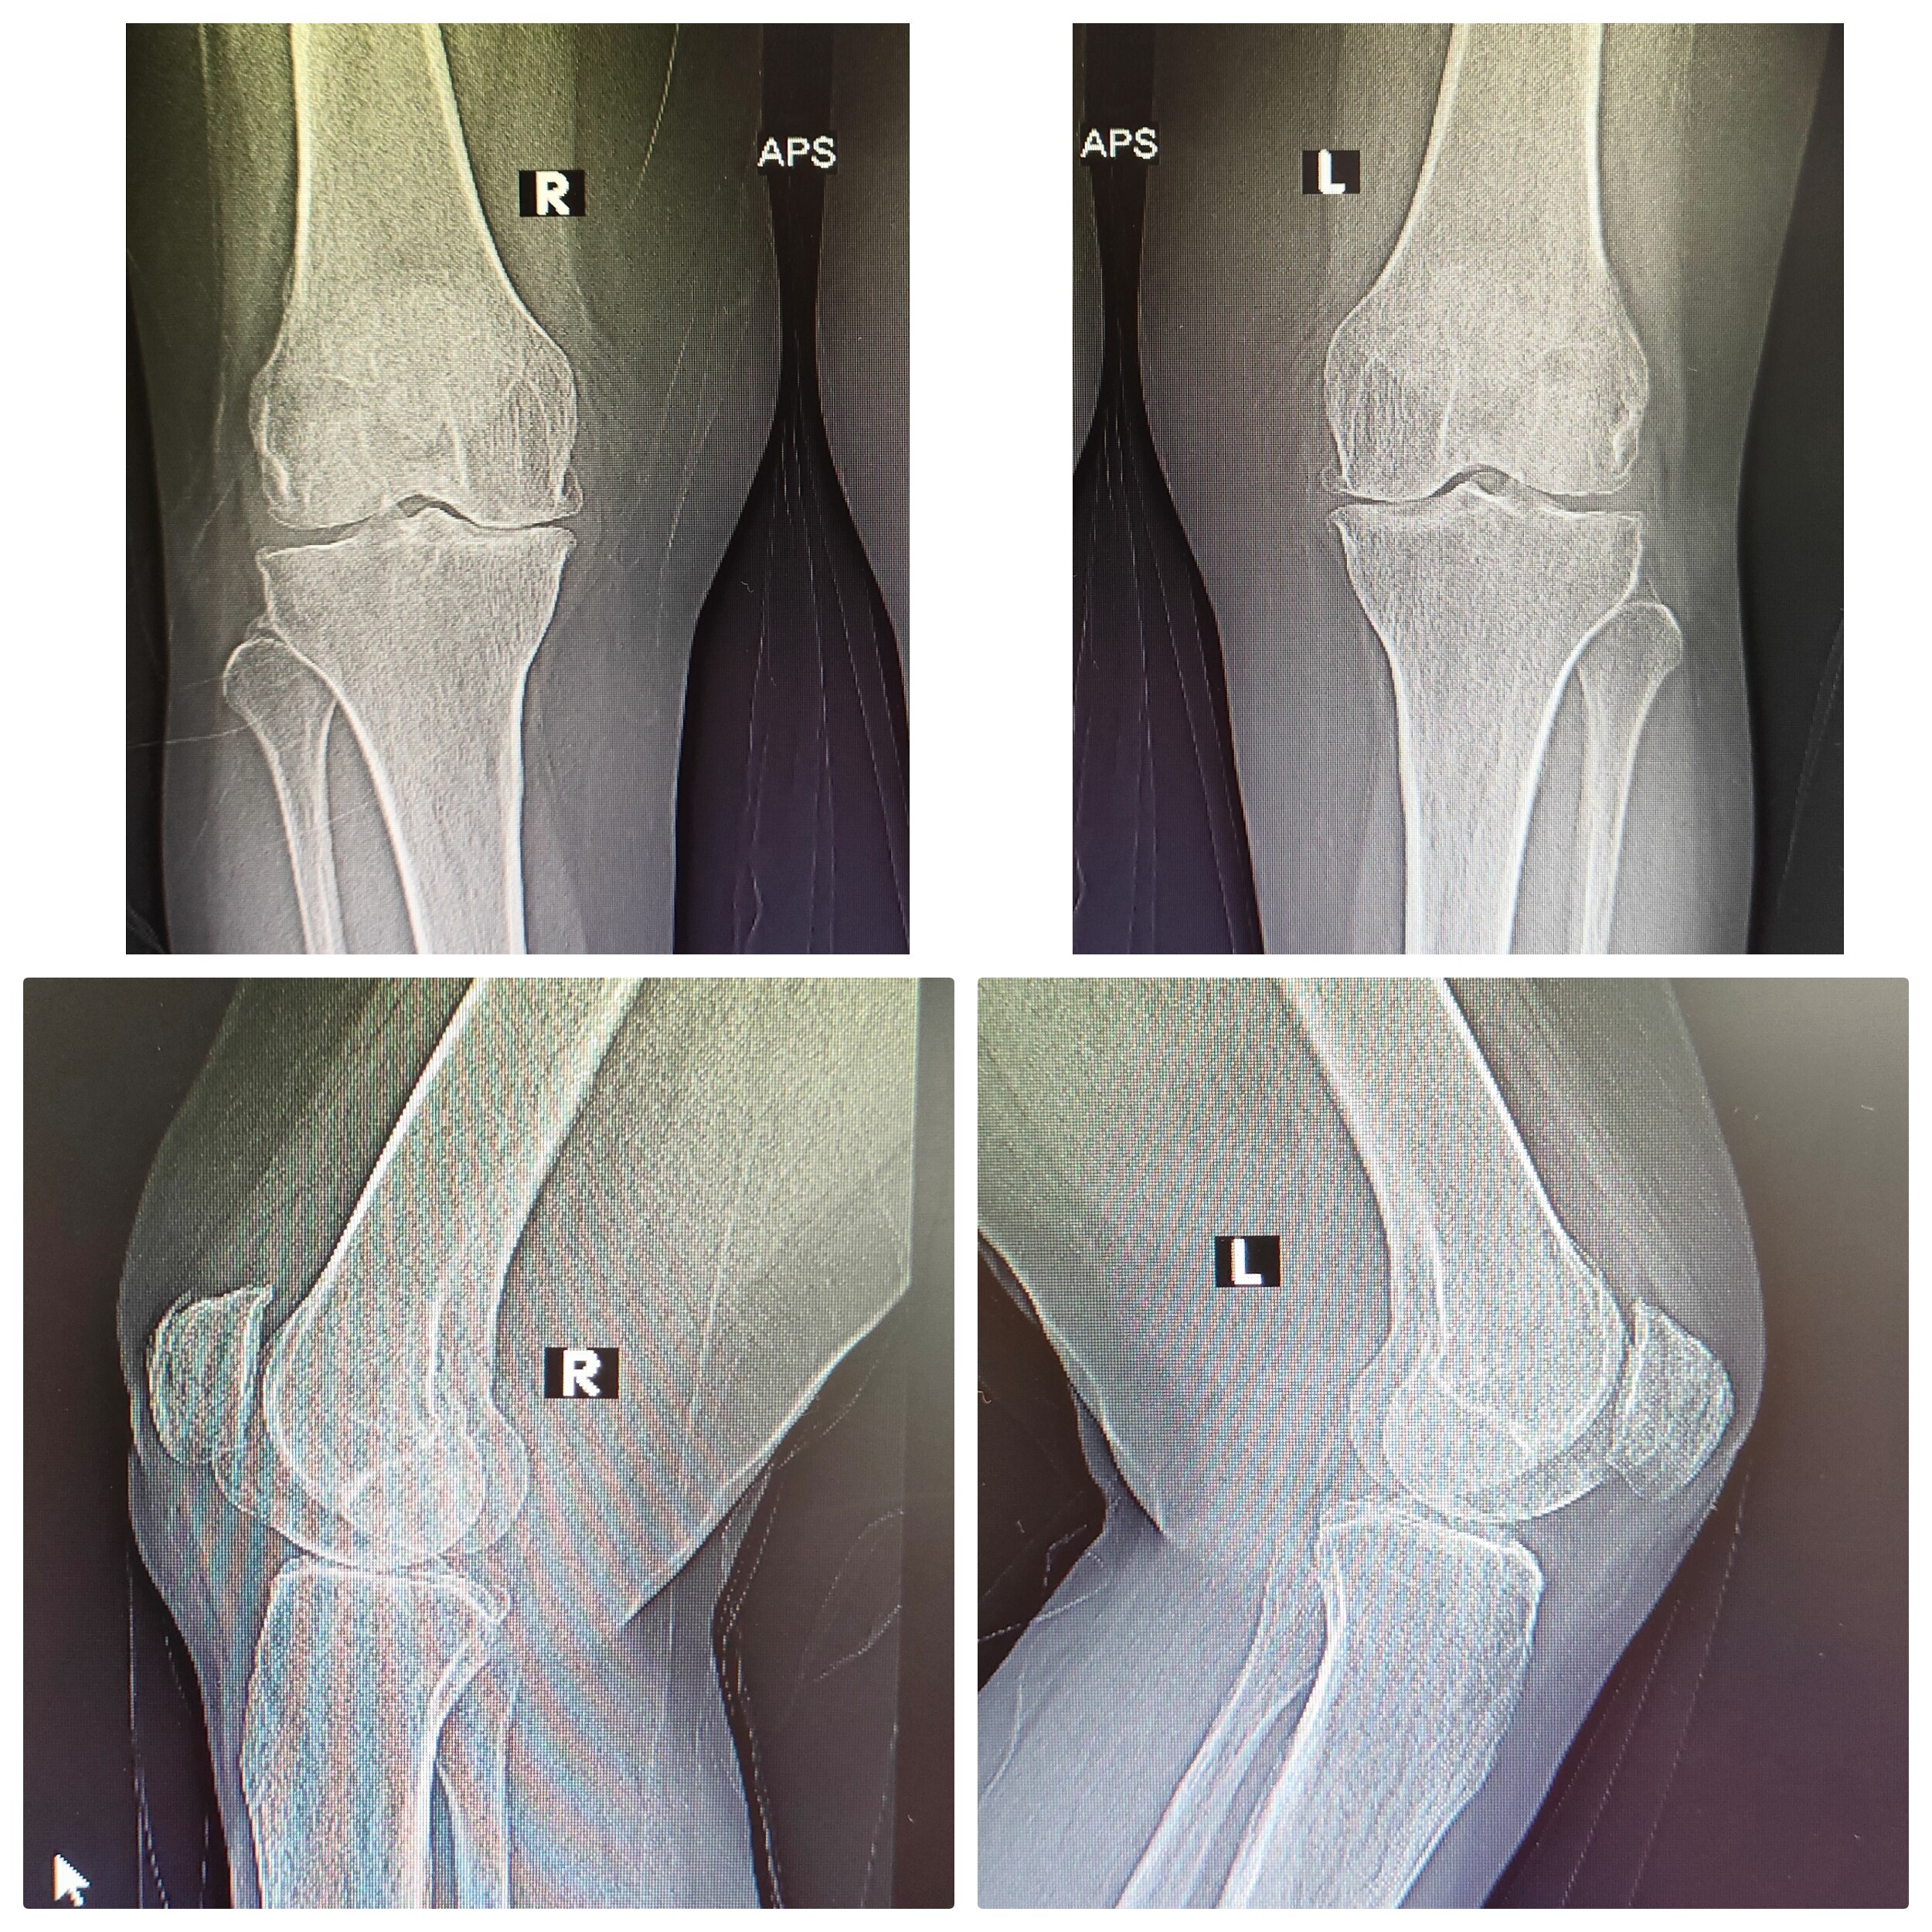

Welcome to the world of orthopedic excellence, where your health and well-being are our utmost priorities. Dr. Chetan Singh , an accomplished orthopedic surgeon, has been a dedicated practitioner in the vibrant city of Bhopal for the past 8 years. His unwavering commitment to providing exceptional orthopedic care has earned him a reputation as a trusted healthcare professional in the region. Meet Dr. Chetan Singh is a highly skilled orthopedic surgeon who has dedicated his career to improving the lives of patients suffering from orthopedic conditions. His educational journey began with the completion of an MBBS degree from Devi Ahilya Vishwa Vidyalaya, Indore, M.P. in 2015, where he laid the strong foundation for his medical expertise. Driven by his passion for orthopedics and a desire to offer the best care possible, Dr.Chetan Singh continued his educational journey. In 2019, he successfully achieved a Master of Surgery (MS) in Orthopedics from Madhya Pradesh Medical Science University, Jabalpur. This rigorous training equipped him with the knowledge, skills, and advanced techniques necessary to diagnose, treat, and manage a wide spectrum of orthopedic conditions.